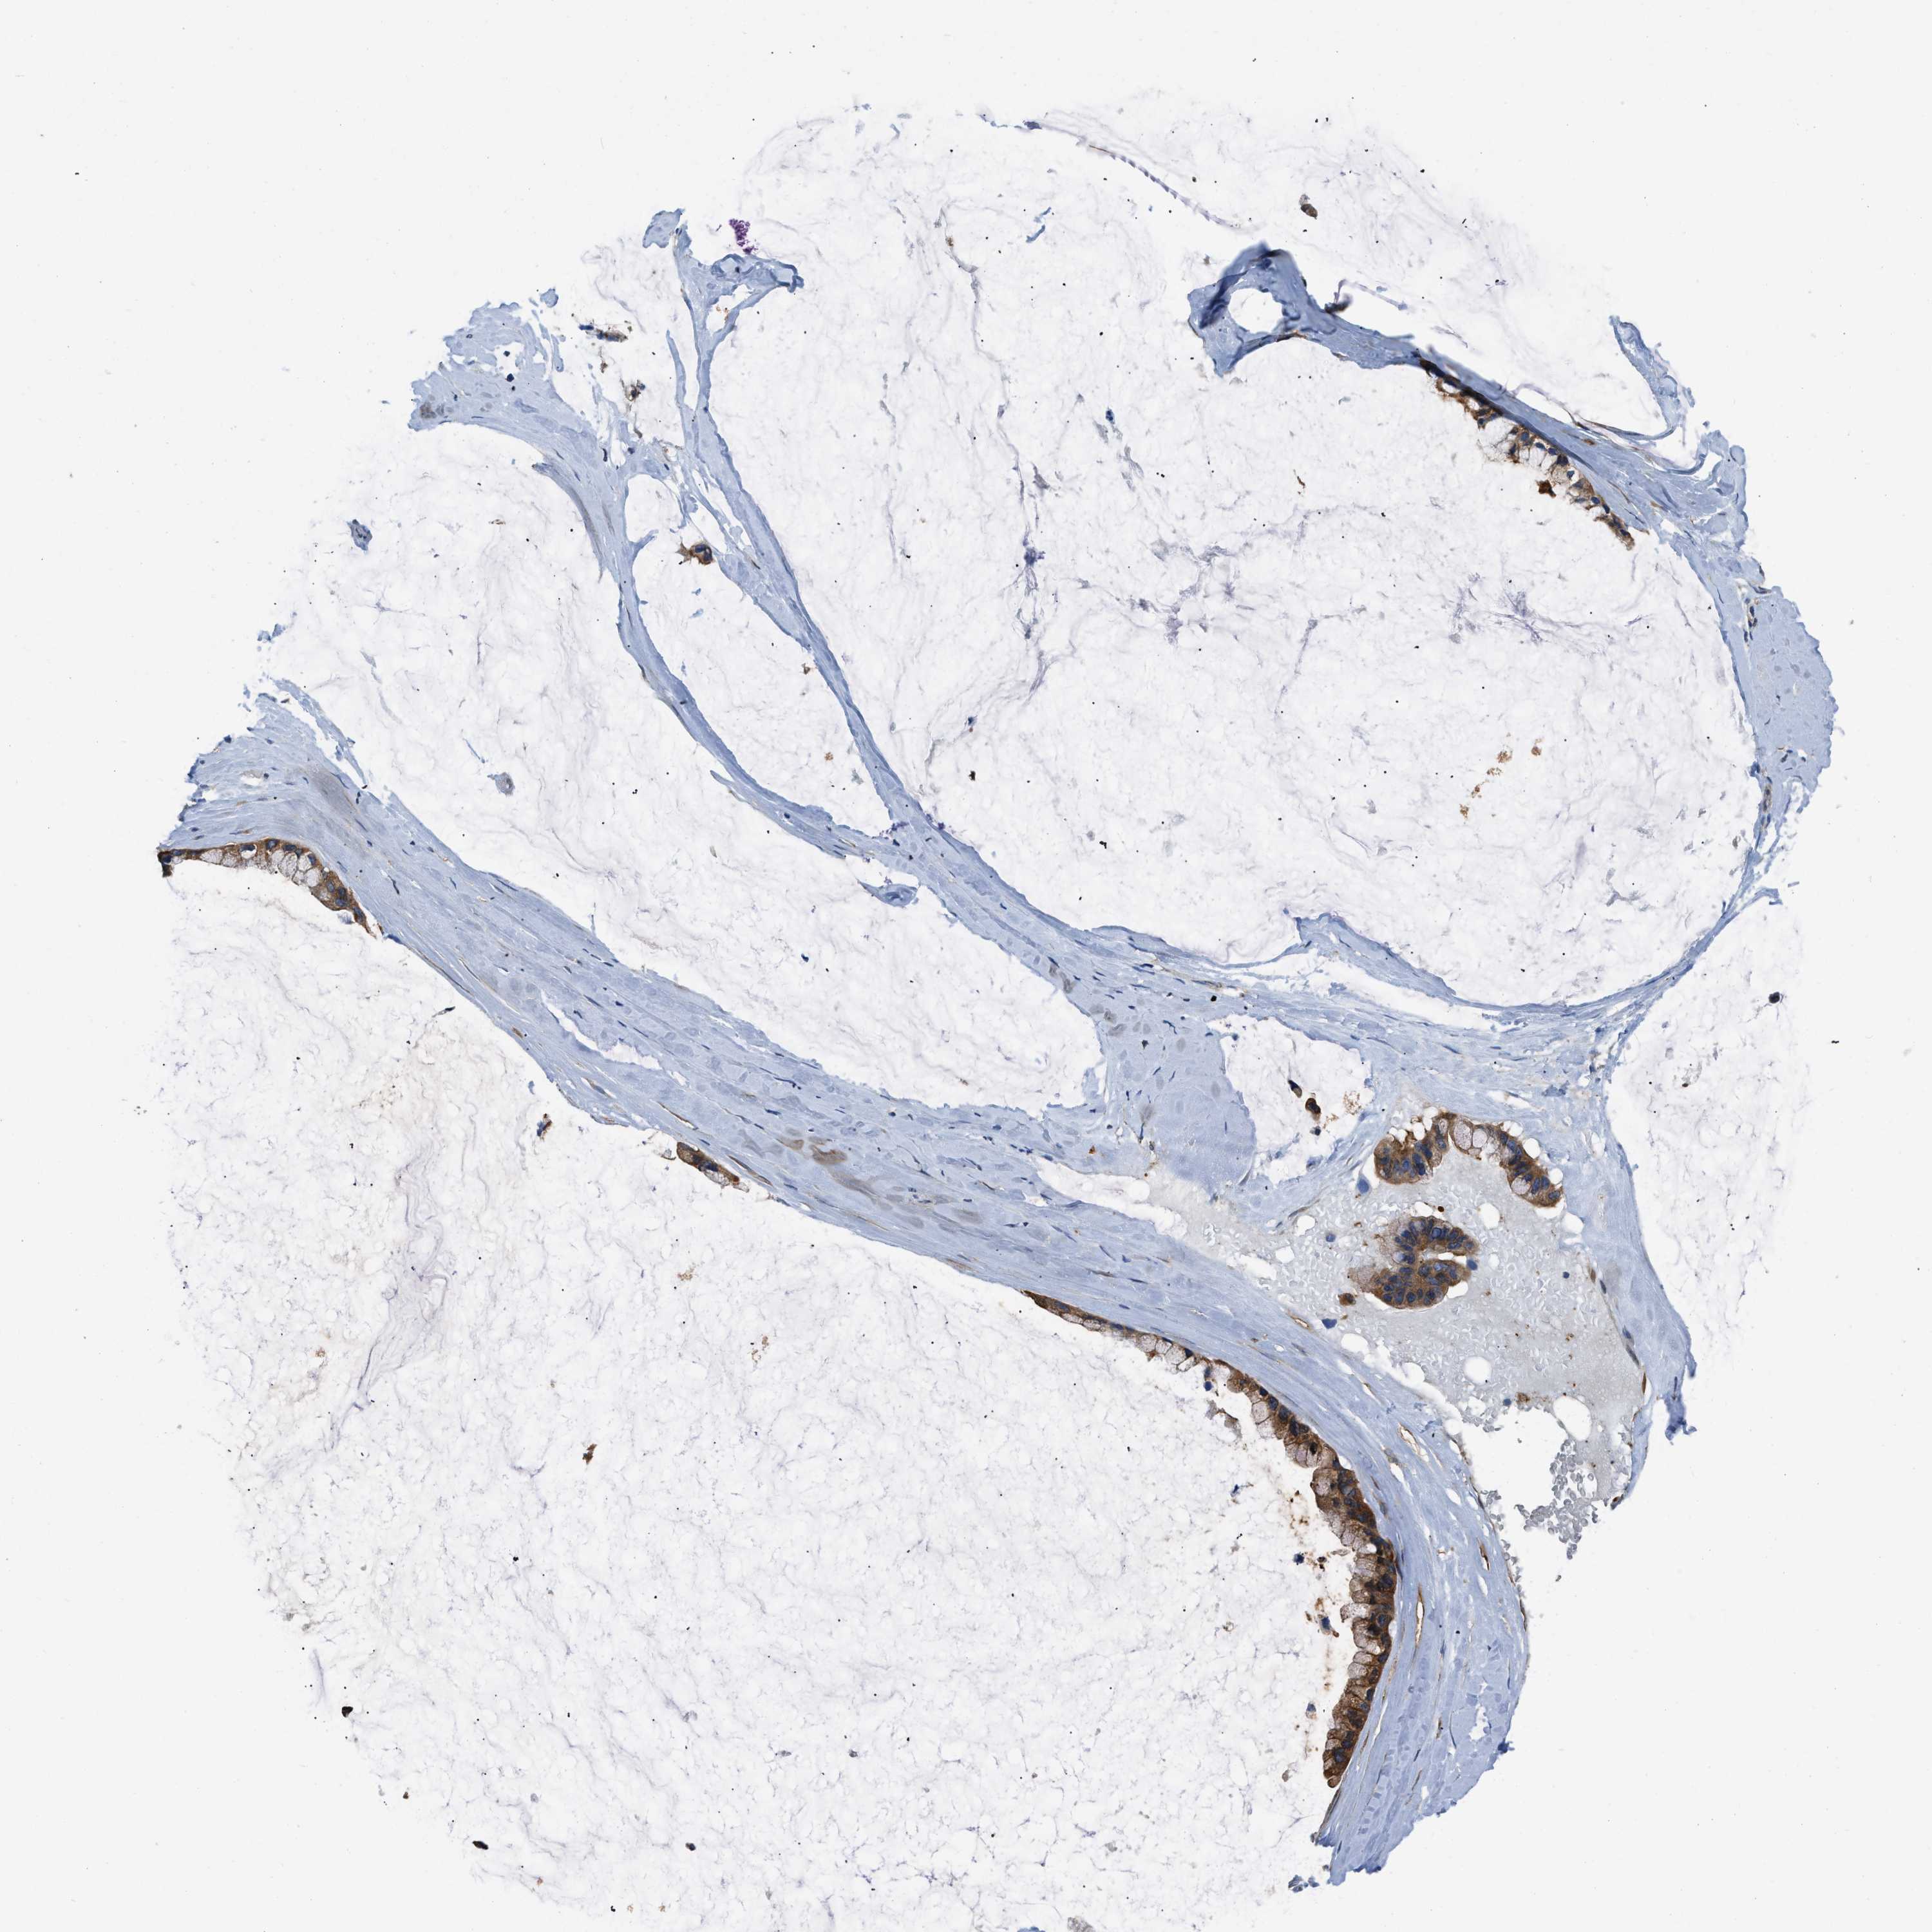

OVARIAN CANCER - Protein expressioni

A mouse-over function shows sample information and annotation data. Click on an image to view it in a full screen mode. Samples can be filtered based on level of antibody staining by selecting one or several of the following categories: high, medium, low and not detected. The assay and annotation is described here.

Note that samples used for immunohistochemistry by the Human Protein Atlas do not correspond to samples in the TCGA dataset.

Antibody stainingi

Antibody staining in the annotated cell types in the current human tissue is reported as not detected, low, medium, or high, based on conventional immunohistochemistry profiling in selected tissues. This score is based on the combination of the staining intensity and fraction of stained cells.

Each image is clickable and will lead to virtual microscopy that enables deeper exploration of all samples and also displays staining intensity scores, fraction scores and subcellular localization as well as patient and tissue information for each sample.

Antibody HPA029501

Antibody CAB019421

Cystadenocarcinoma, serous, NOS

Carcinoma, endometroid

Cystadenocarcinoma, mucinous, NOS

Carcinoma, NOS